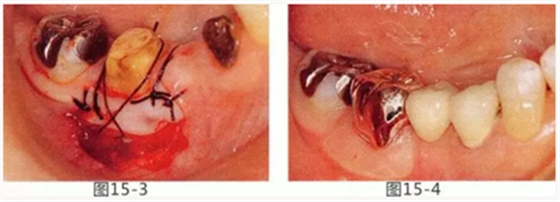

圖15-1,2 右下6近中部的頰系帶延伸到游離齦,附著齦也處于缺失狀態(tài)。如果在這個狀態(tài)下進行修復,會使清潔變得困難,容易引發(fā)牙齦萎縮。

圖15-3 切除系帶。為了獲得附著齦,進行游離齦移植。

圖15-4 手術完成6個月后,佩戴修復體時的狀態(tài)。